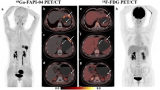

Curium向FDA提交了Cu-64 PSMA I&T的新放射性药研究 (IND)申请

Curium已向美国食品药品监督管理局(FDA)提交了一份Cu-64 PSMA I&T临床实验新药申请(IND),这是一种结合前列腺特异性膜抗原(PSMA)的放射性药物,用于正电子发射断层扫描(PET)检测和定位转移性前列腺癌。 2023-02-23 放射性药物PET/CT

Pentixafor是2015年开发的一种配体,可与细胞表面的CXCR4受体结合。当与核素Ga-68结合时,产生的放射性示踪剂可以在PET成像上显示异常的CXCR4活性。 2023-02-22 PET/CT放射性示踪剂

做完增强CT可以做 18F-FDG PET/CT吗?

增强CT和PET/CT检查均为很重要的影像学检查手段,部分病人往往需要完善多个检查项目,才能达到明确诊断的目的。 2023-02-22 PET/CT